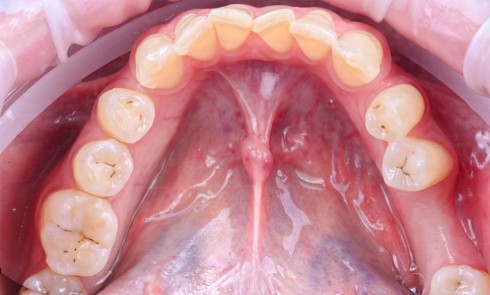

L’implant a été posé alors que la patiente était âgée de 17 ans (le 13 août 2004), à la suite d’un traumatisme entraînant la perte de cette dent (fig. 2a à d), puis la couronne a été posée 5 mois plus tard (le 7 janvier 2005).